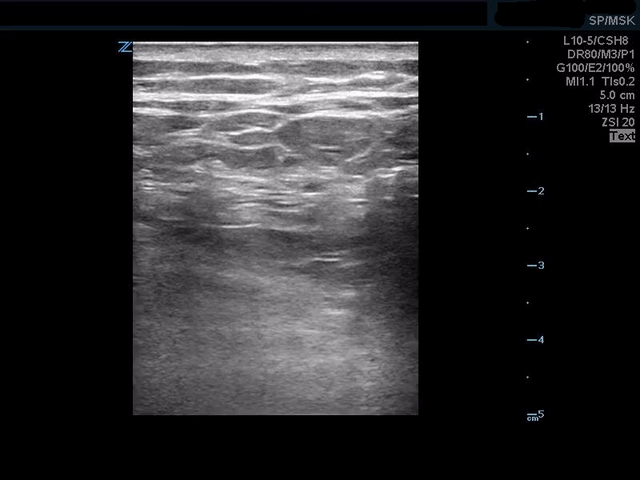

Real time ultrasound shows appropriate spread of anechoic anesthesia across the tissue plane deep to the erector spinae muscles and superficial to the transverse processes. 20mL of Ropivacaine was used and patient experienced almost complete resolution of his rib pain.